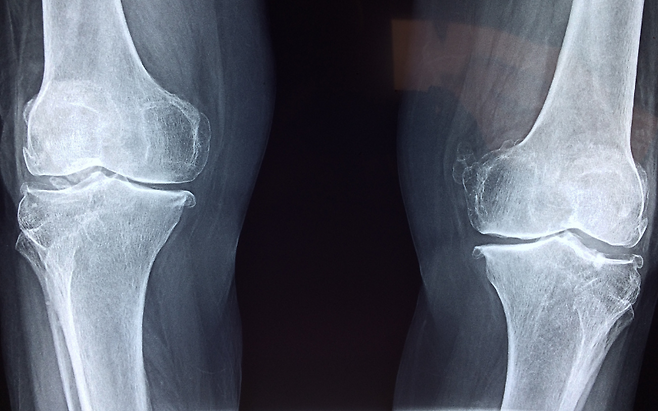

60대 여성이라면 아침 침대에서 일어날 때 “무릎이 쑤신다”는 말이 습관처럼 나오고 있지 않습니까? 관절 안의 연골이 염증과 마찰로 점점 갈려 나가면 통증은 암덩어리처럼 커져 결국 인공관절 수술까지 내몰 수 있습니다.